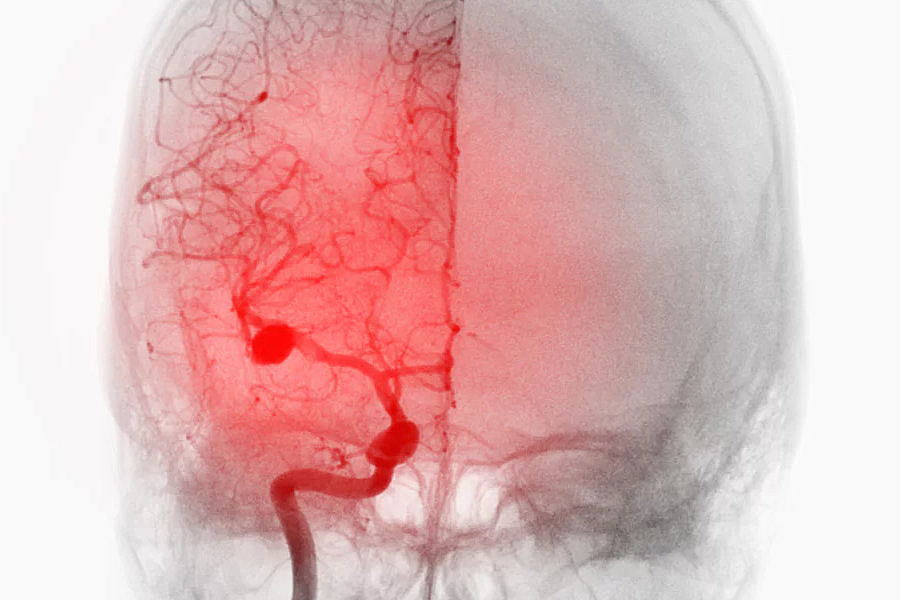

Internationale Lancet-Serie zu Hirnaneurysmen unter UMM-Leitung

Ein internationales Team unter Leitung von Prof. Nima Etminan veröffentlicht eine zweiteilige Lancet Neurology-Serie zu intrakraniellen Aneurysmen.

Apotheken Umschau: Prof. Dr. med. Nima Etminan über Hirnaneurysmen

Diagnose Hirnaneurysma – wie gefährlich ist es und wie wird behandelt? Darüber sprach die Apotheken Umschau mit dem Klinikdirektor der Neurochirurgische Klinik.